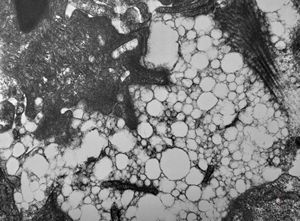

jejunum … lipid malabsorption

F,8m. | lipid malabsorption - large lipid droplets in enterocytes … semithin section

lipid malabsorption - large lipid droplets in enterocytes … semithin section

lipid malabsorption - large lipid droplets in enterocytes and propria … HE